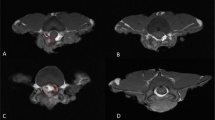

Magnetic resonance imaging

Magnetic resonance imaging (MRI) was generated 1 month after spine surgery. These mice were anesthetized with isoflurane and scanned at the T11-L4 spine. MRI images were collected using a Bruker 7.0 T Micro-MR imaging system and a Multi-Slice Multi-Echo T2-weighted imaging (MSME T2WI) sequence. The time of repetition (TR) for MR images was 4391 ms. All parameters (TE, 33.0 ms; layers, 40; thickness, 0.5 mm; and interlayer space, 0) were followed once for a total of 10 min 18 s 120 ms per set. The epidural scar area was measured by ImageJ software.

In a mouse model of laminectomy, the mice were evaluated for the formation of epidural scarring 28 days after the operation. As illustrated in Fig. 6A (Supplementary Fig. 3), MRI recorded severe adhesion between scar tissue and the dura mater in the mice that underwent spine operation. Hydrogels alone partially relieved the formation of fibrosis. Compared with DNase I absorbing in the gelatin sponge, temperature-sensitive hydroxypropyl chitin hydrogels loaded with DNase I showed significantly fewer epidural scars (Fig. 6B). Furthermore, the mice treated with hydrogels loaded with DNase I developed significantly lower levels of inflammation (Fig. 7A, Supplementary Fig. 4) and less collagen fiber deposition (Fig. 7B, Supplementary Fig. 5). These results suggested that hydrogels loaded with DNase I effectively decreased epidural fibrosis in a mouse model of laminectomy.